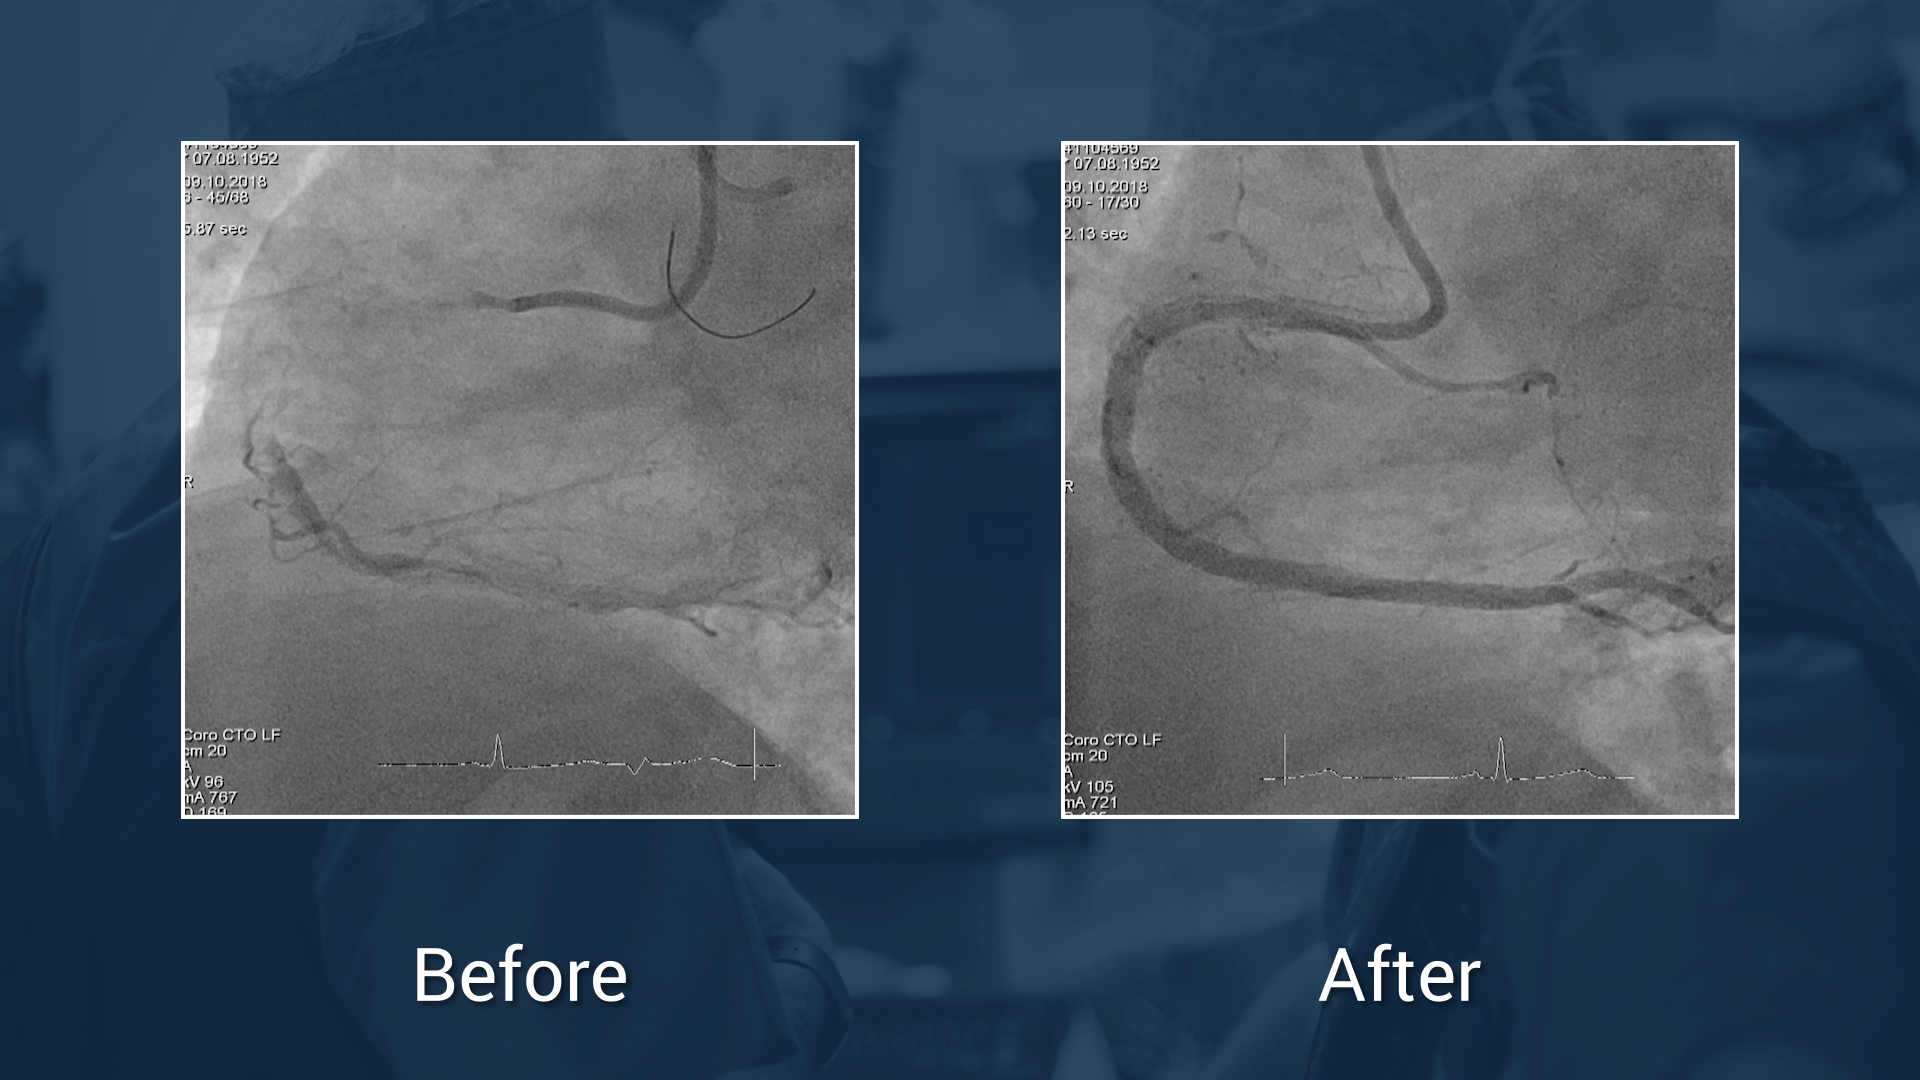

Protocole:

• OptiRAY® (ioversol)

• Concentration: 350 mgl/mL

• Volume: 170 ml

Total Time: 77 min

Exposure Time: 36 min

Exposure: 1704 mGy

Workshop on Complex PCI (UHZ - Bad Krozingen)

We are pleased to announce you that the Guerbet Masterclass which took place on October 2018 at the UHZ (Bad Krozingen, Germany) is available online for all participants and incathlab members. ...